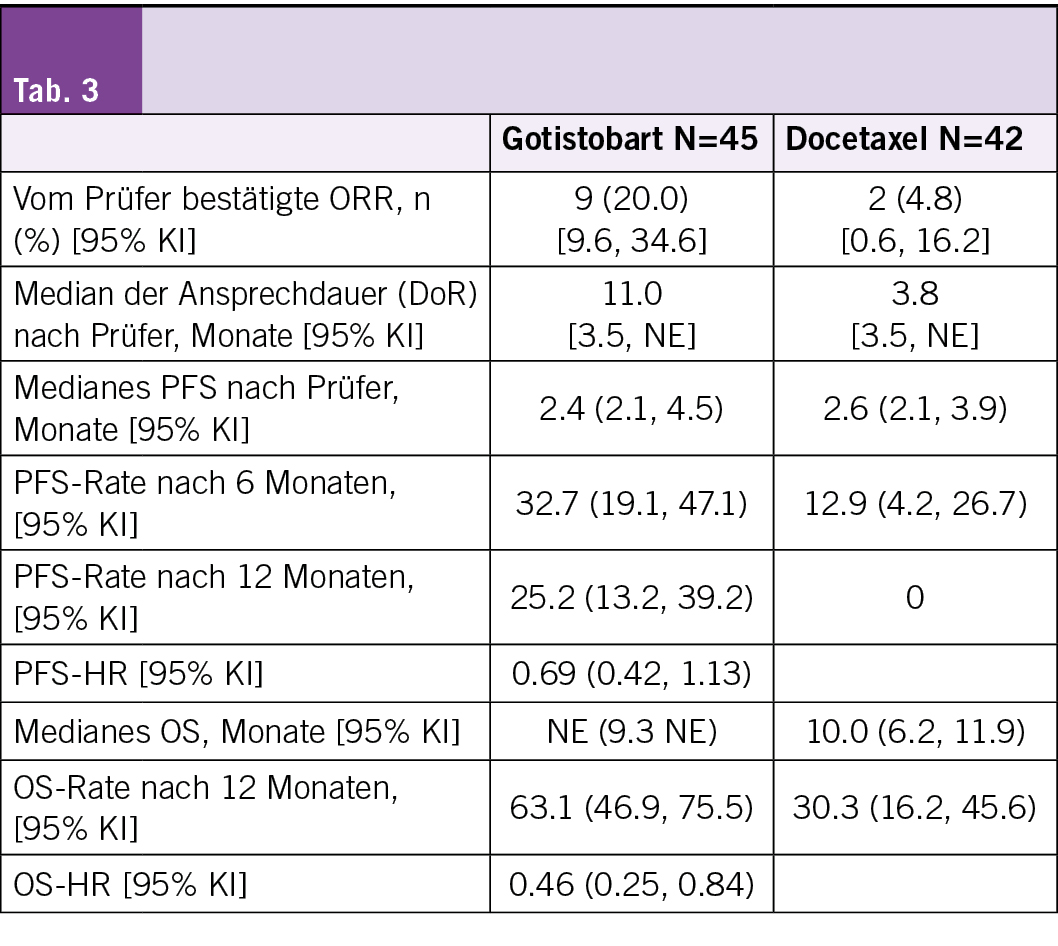

Anhaltende Antitumoraktivität mit klinisch bedeutsamem Überlebensvorteil

Kai He, et a. 3O Anti-tumor activity of gotistobart compared to docetaxel in patients with metastatic squamous non-small cell lung cancer (sqNSCLC) progressing on PD-(L)1 inhibitors: Stage 1 PRESERVE-003 phase III trial

Vorbemerkungen

Gotistobart, ein neuartiger Antikörper, der Treg-Zellen in der Tumormikroumgebung gezielt durch CTLA-4-Hemmung angreift, hat in einer Phase-III-Studie bei Patienten mit fortgeschrittenem sqNSCLC unter PD-(L)1-Inhibitoren einen klinisch relevanten Überlebensvorteil gezeigt (HR: 0,46 [95 % KI: 0,25–0,84]; #OA01.01, NACLC 2025). Die Autoren präsentieren weitere Wirksamkeitsergebnisse aus Phase 1 dieser Studie.

Studiendesign

• Patienten mit metastasiertem NSCLC, deren Erkrankung unter PD-(L)1-Inhibitoren und platinbasierter Chemotherapie fortgeschritten war, wurden im Verhältnis 1:1 randomisiert und erhielten entweder Gotistobart (6 mg/kg mit zwei Initialdosen von 10 mg/kg alle drei Wochen) oder Docetaxel (75 mg/m² alle drei Wochen).

Behandlungsresultate

• Es wurden 217 Patienten in Phase 1 aufgenommen, darunter 87 Patienten mit sqNSCLC, die randomisiert Gotistobart (N = 45) oder Docetaxel (N = 42) erhielten, bei einer medianen Nachbeobachtungszeit von 14,5 Monaten.

• Das mediane PFS war ähnlich (2,4 Monate vs. 2,6 Monate), aber die 12-Monats-PFS-Rate betrug 25 % für Gotistobart und 0 % für Docetaxel, mit einer HR von 0,69 (95 % KI, 0,42, 1,13) zugunsten von Gotistobart.

• Die bestätigte ORR betrug 20 % (95 % KI: 9,6, 34,6) für Gotistobart und 4,8 % (95 % KI: 0,6, 16,2) für Docetaxel.

• Die mediane DoR betrug 11 Monate für Gotistobart gegenüber 3,8 Monaten für Docetaxel.

• Weitere Wirksamkeitsdaten sind in der Tab. 3 aufgeführt.

Fazit

Die Gotistobart-Monotherapie bietet eine chemotherapiefreie Behandlung für Patienten mit sqNSCLC, bei denen eine Anti-PD-(L)1-Therapie nicht mehr wirkt. Laut den Studienautoren zeigt sie einen deutlichen Überlebensvorteil gegenüber Docetaxel und erfüllt einen wichtigen Bedarf an wirksamen Therapieoptionen. Die zulassungsrelevante Phase-2-Studie rekrutiert derzeit weltweit Patienten.